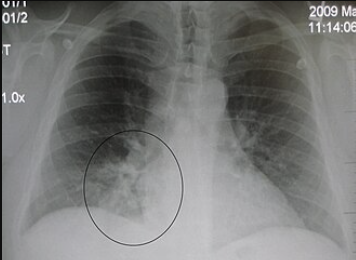

• Lower Respiratory Tract Infections (Parenteral Administration): Cefuroxime (IV/IM) is indicated for community-acquired pneumonia and other lower respiratory infections caused by susceptible bacteria. (Parenteral Administration)

• AP Chest X-ray showing right lower lobe pneumonia

• Cefuroxime is effective against S. pneumoniae, H. influenzae (including β-lactamase-producing strains), Staphylococcus aureus (MSSA), Streptococcus pyogenes, and Klebsiella in the lungs.2,5,6

• The Infectious Diseases Society of America (IDSA) and American Thoracic Society have endorsed cefuroxime as an option for hospitalized community-acquired pneumonia.

• In practice, IV cefuroxime for pneumonia is often paired with a macrolide to cover atypical pathogens, or a respiratory fluoroquinolone might be used instead; however, cefuroxime is a reasonable β-lactam choice for many typical pneumonia cases.